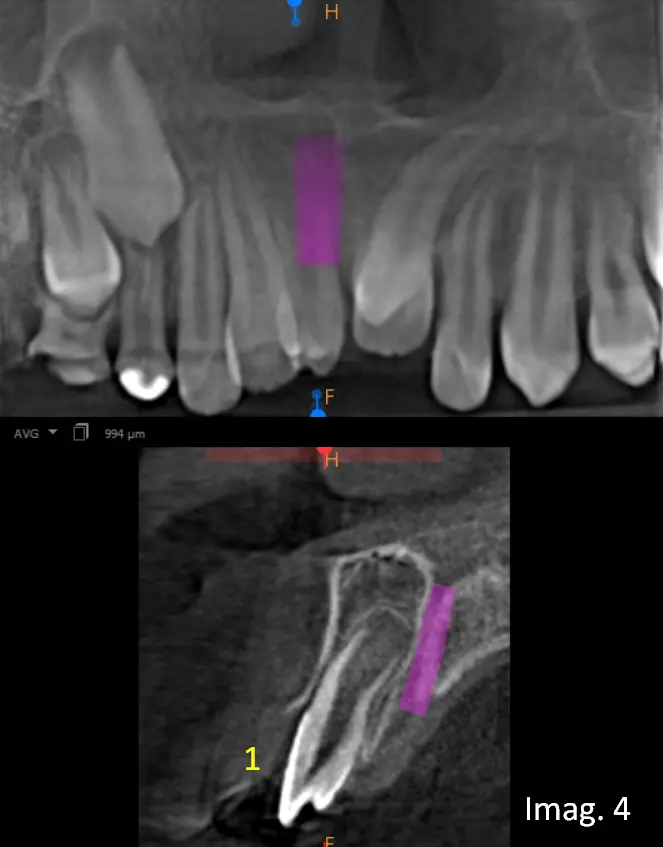

En los cortes transaxiales (imágenes 4 y 5) se visualiza el primer Mesiodens ubicado en posición vestibular, próximo al reborde alveolar, clínicamente erupcionado, mientras que el segundo Mesiodens se encuentra localizado en posición palatina, intraóseo, no erupcionado, en íntima relación con las raíces de los incisivos centrales superiores.